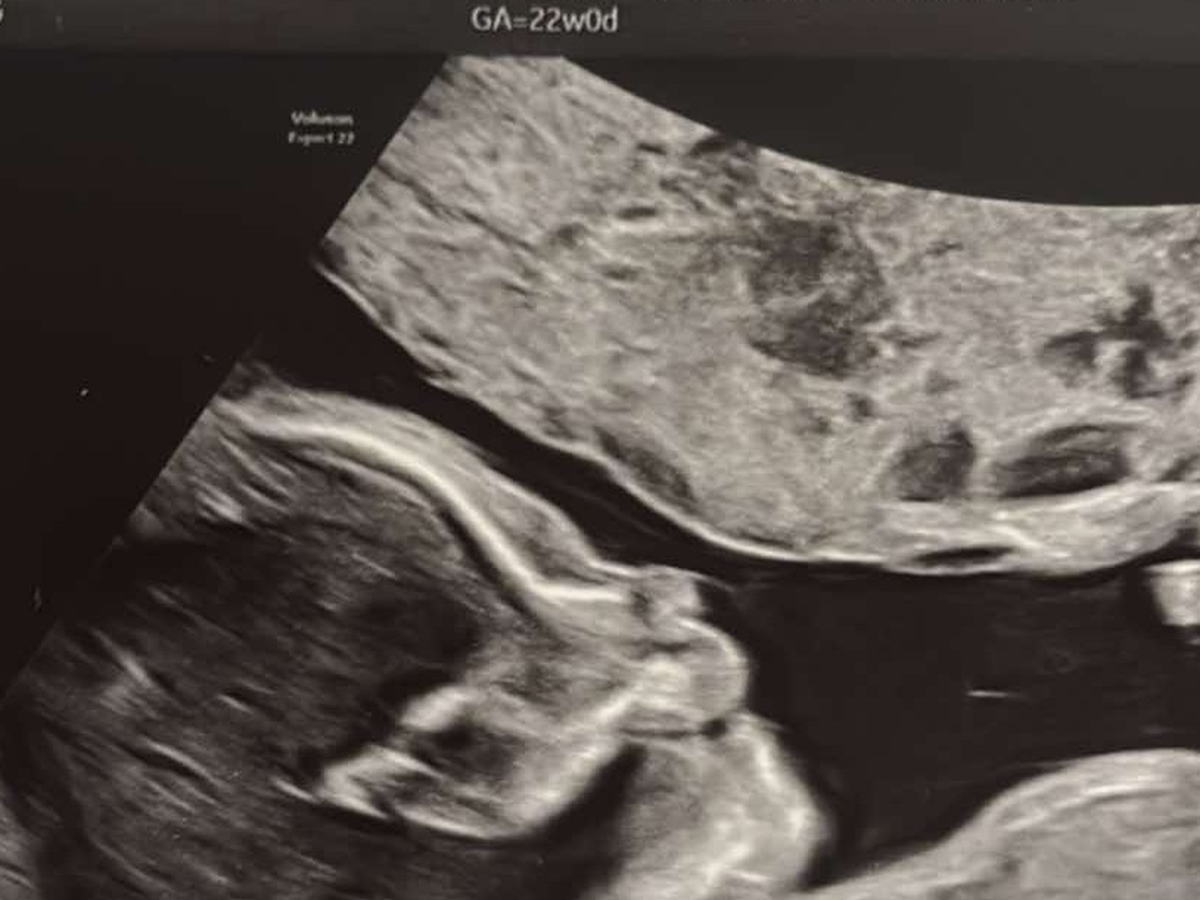

My name is Serenity I want to thank you for reading my unborn daughter's story. I’m 22 weeks pregnant currently, and our precious, miracle baby needs specialized care.

We are expecting baby #5, Brayleigh. We just spent the last few nights at St. Vincent Women’s High-Risk Unit. Brayleigh's right atrium of her heart is enlarged due to part of her tricuspid valve being stuck open. This causes her blood to go the wrong way, causing not enough blood to get to her lungs and not enough oxygenated blood getting to the rest of her body. I also have what they call placenta previa, which is where the placenta is covering the cervix, causing it to be high risk.

I will be hospitalized in 5 weeks at which time Brayleigh will be delivered by caesarean, three months early. If certain problems arise I may be hospitalized again before the five weeks. Brayleigh will have to have surgery to correct the flap on her heart.